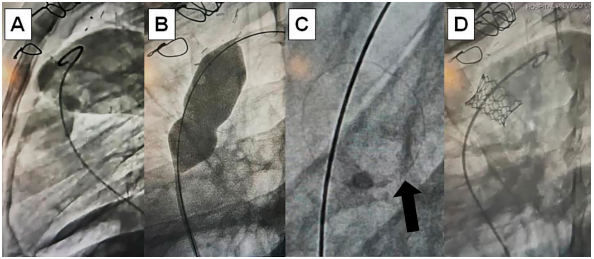

Fig. 1.

(A) Angiografía de bioprótesis Epic Supra® (St Jude Medical, USA) disfuncionante en posición pulmonar en proyección oblicua lateral izquierda estricta 90°. (B) Balón no complaciente de ultra-alta presión para producir fractura intencional del anillo valvular. (C) Anillo valvular fracturado(Flecha). (D) Angiografía en la misma proyección inicial: válvula balón expandible Myval® (Meril, India) implantada con técnica “válvula en válvula” en posición pulmonar

Imagen 1

La estrategia de ruptura/remodelación del anillo valvular y el implante “válvula en válvula” posterior se realizó según técnicas usuales estandarizadas. (5) El balón no complaciente de ultra-alta presión seleccionado para la fractura, fue del mismo tamaño o hasta 1,5 mm mayor que el diámetro nominal de la bioprótesis a fracturar. La presión de ruptura aplicada fue la necesaria para lograr el objetivo y no superó las 12 atmósferas (Figuras 1 y 2). El diámetro de la válvula balón expandible a implantar fue seleccionado entre 0,5 y 2 mm mayor que el diámetro nominal/comercial de la VBP. Todos los pacientes recibieron aspirina 100 mg/día indefinidamente luego del implante valvular.